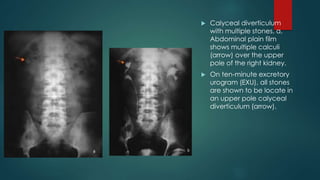

 Calyceal diverticulum

with multiple stones. a,

Abdominal plain film

shows multiple calculi

(arrow) over the upper

pole of the right kidney.

 On ten-minute excretory

urogram (EXU), all stones

are shown to be locate in

an upper pole calyceal

diverticulum (arrow).